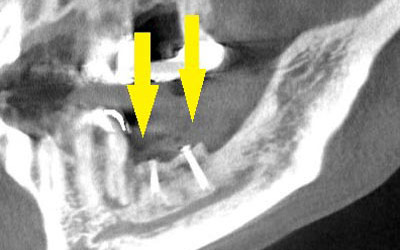

• 写真のように、CTで見ると、骨吸収の様子が良く分かり、下顎骨の中を通る神経近くまで骨がありませんでした。

• さらに、CTで、別な方向から見ると、黄色矢印のように骨が吸収されていて、緑色矢印で示される神経の通る管に迫り、インプラントが埋入できるような骨量はありませんでした。

• インプラントを埋入するために、骨を増やす方法はいくつかありましたが、この場合、患者様ご自身の骨をブロック状で移植するのが最も適していると判断し、自家骨移植術を行ないました。患者様ご自身の下顎前歯の下方から骨を採取して、骨がなかった部位に移植し、スクリューで固定したCT画像です。黄色矢印部分が、2つの骨片を移植して、固定したところです。